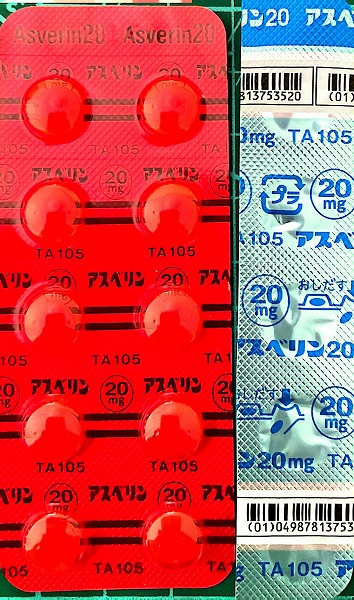

2021.11.13より 西原クリニック 0968-62-0622

2024.7.12(金) 2回目のコロナ感染 7.16(火)検査で陽性